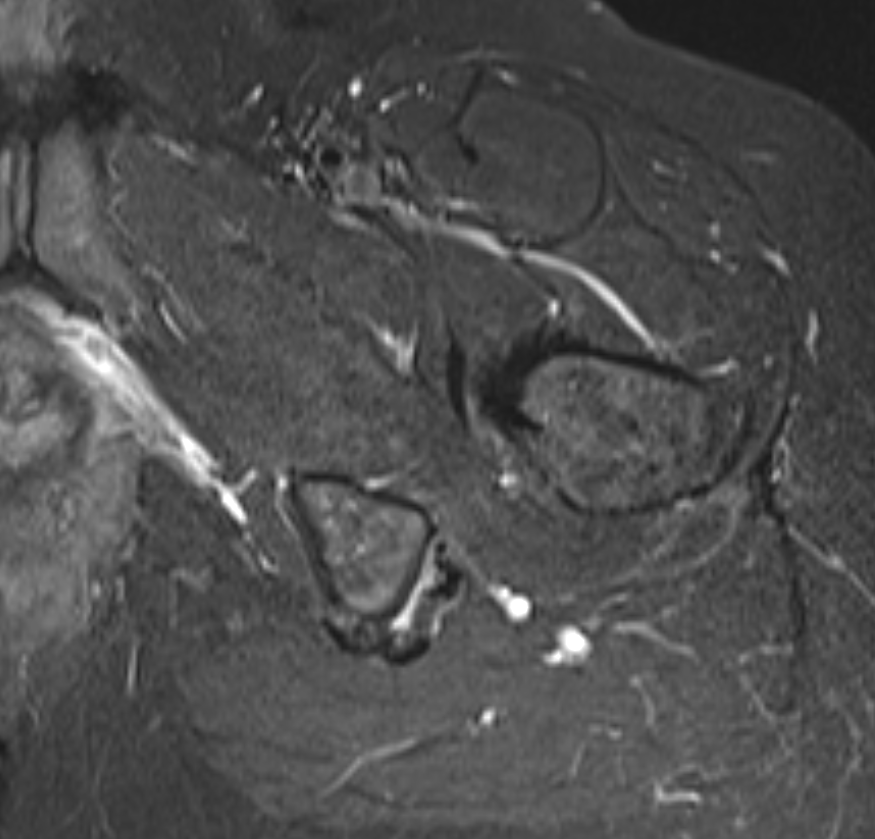

Hamstring (*) with sciatic nerve lateral to hamstring (blue vessiloop)

Identify and release proximal hamstring tendon

Stump of the conjoint tendon (*)